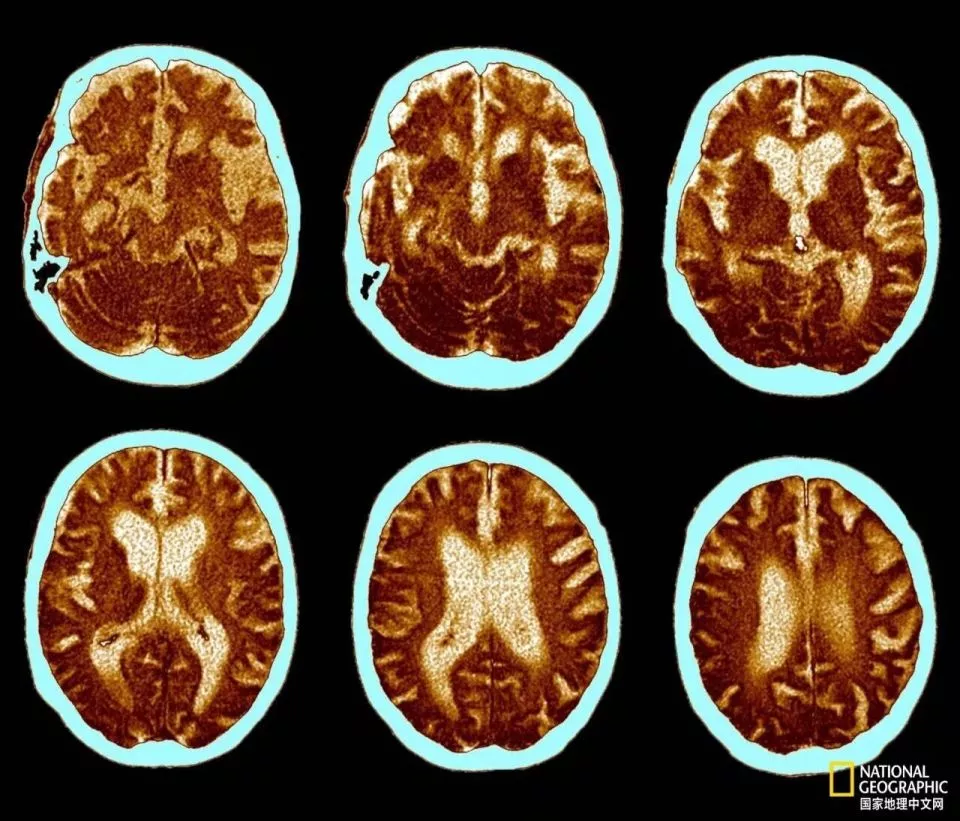

这是一位74岁阿尔茨海默病患者的脑部扫描图,清晰地揭示了该病如何导致大脑萎缩。图中可见脑室腔扩大,以及淡蓝色区域增宽,这些都是脑萎缩的典型表现。这种大脑萎缩会引发记忆力减退、意识模糊以及性格改变等症状。|国家地理图片集